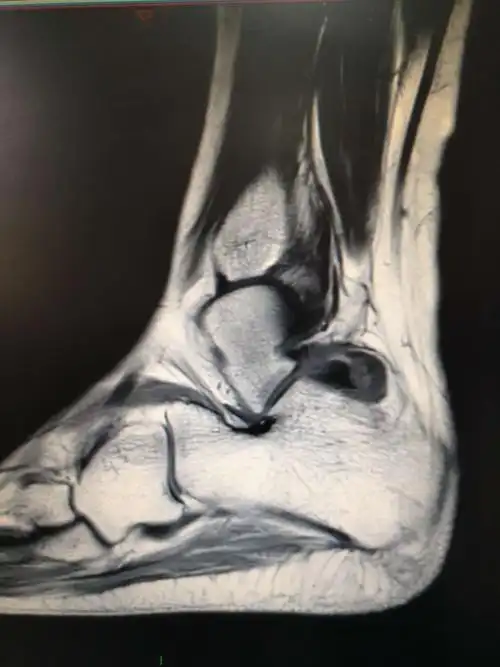

安医骨病骨肿瘤科胡勇教授团队 一例踝关节畸形治疗案例分享

踝关节滑膜软骨瘤病

踝关节镜下切除腱鞘巨细胞瘤